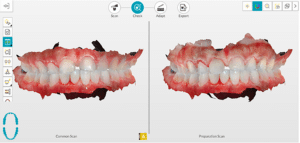

Mme AB vient en consultation pour deux raisons. La première est une douleur intense à chaque fois qu’elle boit ou mange froid. La deuxième est l’apparence de son sourire. Elle trouve que ses dents ont « raccourci » et qu’elles « s’effritent ». C’est devenu un complexe handicapant. À L’examen clinique on observe (Fig.1a, b, c, d, e) une usure vestibulaire de toutes les dents : plus prononcée au maxillaire et assez légère sur les incisives mandibulaires, une classe III canine et molaire droite, une classe I canine et molaire gauche avec une légère déviation des milieux et une usure importante des faces palatines du bloc IC maxillaire ainsi que des faces occlusales de 16 et 26. On constate aussi que les faces occlusales des autres dents sont moins touchées en apparence. On observe que les amalgames de 36 et 48 sont en relief par rapport à la dent support. Il est raisonnable de supposer qu’à l’origine ils devaient obturer une cavité et donc être à l’intérieur de la dent. Ceci témoigne donc aussi d’une forte usure sur 36 et 46. On observe enfin que les courbes de Spee sont complètement plates.

Fig.1a, b, c, d, e : Examen clinique.

Fig.1b.

Lors de cette première consultation, en plus de l’examen clinique, on réalise une empreinte optique (Fig.2).

Fig.2.

Elle a deux buts. Le premier relève de la communication : il est plus facile pour la patiente de se rendre compte de l’état d’usure de ses dents avec une image 3D en plus des photographies et du miroir de courtoisie. Le deuxième but est l’analyse de l’occlusion. Grâce au logiciel d’exploitation (ici, Dexis IS Scan Flow), on se rend bien compte que l’occlusion est serrée avec des contacts extrêmement forts à droite (en rouge sur le Scan Flow). Il est alors facile de conclure et d’expliquer dès à présent à la patiente qu’il est impossible de restaurer son sourire dans cette situation occlusale. Pour redonner de la hauteur aux dents antérieures il faut de la place, créée soit par soustraction en préparant les dents antérieures, soit par addition en relevant la hauteur des dents postérieures. La patiente fait rapidement son choix. Pour nous, cela signifie qu’il va falloir augmenter la DVO.